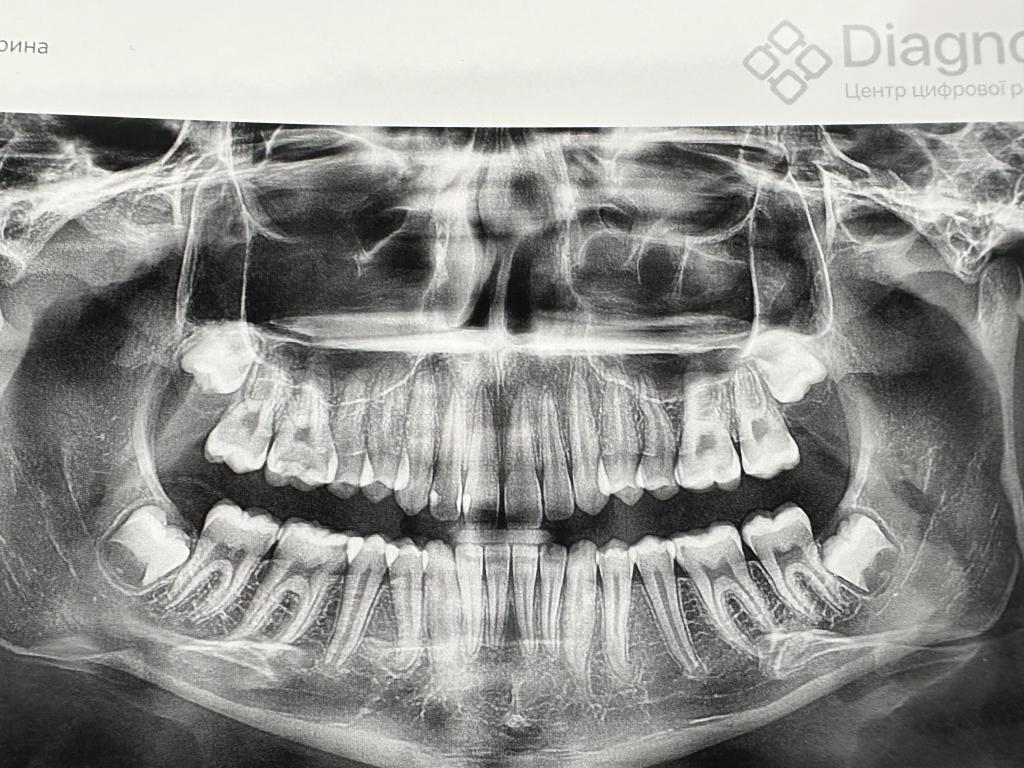

Нажмите на изображение для увеличения

Название: IMG_7428.jpg

Просмотров: 128

Размер:	137.7 Кб

ID:	13600570Добрый день, подскажите пожалуйста, удаляла ретинированные 8-ки, доктор уточнил есть ли ребенок, сколько лет и рекомендовал сделать снимок, дочке 15, сделали снимок, доктор говорит надо удалять 8-ки где-то через пол года, так как типа им места не будет скорее всего и проще удалить сейчас. Меня это как-то пугает, это же надо будет резать и все такое. И как вообще знать надо ли их удалять.

Вложение 13600570Добрый день, подскажите пожалуйста, удаляла ретинированные 8-ки, доктор уточнил есть ли ребенок, сколько лет и рекомендовал сделать снимок, дочке 15, сделали снимок, доктор говорит надо удалять 8-ки где-то через пол года, так как типа им места не будет скорее всего и проще удалить сейчас. Меня это как-то пугает, это же надо будет резать и все такое. И как вообще знать надо ли их удалять.

Лично я диаметрально противоположного мнения. Я не сторонник удаления восьмерок без явной на то необходимости, хотя с определенной периодичностью провожу эти операции. Удаление 8-к в зачатках имеет свои особенности, и порой, их удалить сложнее, чем ретенированную 8-ку со сформированными корнями. А проводить такую непростую операцию ребенку и взрослому – это 2 большие разницы, в первую очередь – психологическая.

В вашем случае по снимку у 8-к относительно правильное положение… сделайте в 18 лет контрольный снимок, если к тому времени сами не прорежутся))

В общем, я бы на вашем месте не спешил с удалением. Удалить всегда успеете, а лишняя жевательная единица никому не помешала бы…

Дочке удаляли все восьмерки. С одной стороны удалили в 14 лет. Корни еще не сформировались и очень все прошло быстро. С другой стороны удаляли в 15 лет. Уже было сложнее и дольше. Удаляли по 2 штуки с одной стороны. У дочки было показание, так как носили брекеты и восьмерки лежали неправильно, все сдвинули бы. Больно было только первый день после удаления, потом все нормально. Но .... это дорого )

У сына были полностью ровные зубы. Восьмерки вылезли и сдвинули передние зубы. Потом они выросли не полностью и находились частично под десной. Из-за этого было постоянное воспаление. Срезали этот десневой капюшон и все стало нормально. Врач сказал, что зубы очень крепкие.